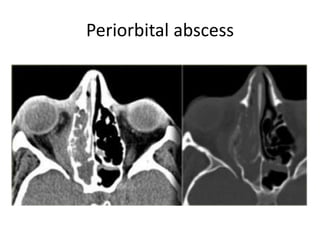

Periorbital abscess

• Complications

– Venous thrombosis of the superior and inferior

ophthalmic vein

– Cavernous sinus thrombosis and cavernous-

carotid fistula in certain fungal sinusitis

(e.g.aspergillosis)

Orbital and periorbital cellulitis

• A 'red hot eye' and proptosis

• Orbital VS periorbital cellulitis ->

>> the orbital septum <<

• Periorbital cellulitis

– The orbital septum and the superficial part

– OPD—PO ATB

• Orbital cellulitis

– the structures posterior to the septum are also involved.

– IPD--IV ATB